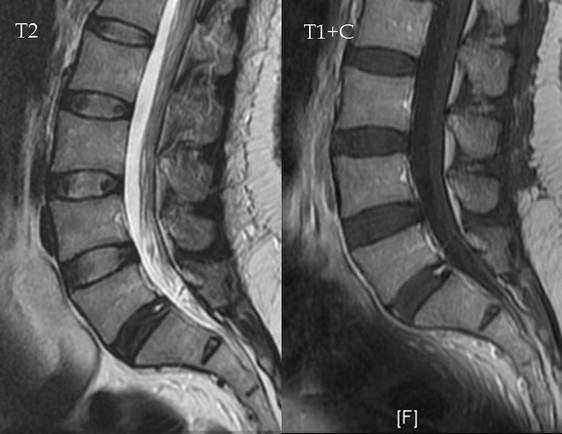

Самый информативный метод диагностики поясничного смещения дисков — МРТ. На полученных изображениях отчетливо визуализируются все поврежденные структуры: межпозвонковые диски, позвонки, мягкие ткани, спинномозговые корешки, кровеносные сосуды. С помощью МРТ можно установить локализацию выпячивания, оценить его форму и размеры. Также исследование позволяет выявить типичные признаки поясничного остеохондроза, спровоцировавшего формирование грыжи в этом отделе.

Беременность не является противопоказанием для проведения МРТ. Не отмечено случаев негативного воздействия магнитного поля на внутриутробное развитие плода. Но во время диагностической процедуры возможно повышение температуры околоплодных вод. Поэтому МРТ не проводится в 1 триместре, когда происходит закладка органов всех систем жизнедеятельности эмбриона.

На ранних сроках вынашивания ребенка этот метод диагностики используется только по жизненным показаниям. Обычно смещение дисков выявляется в ходе безопасного ультразвукового исследования с учетом результатов общеклинических анализов.